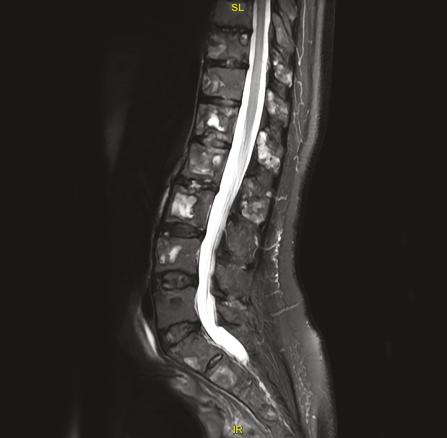

Les images IRM (fig. 1 et 2) du rachis montrent de multiples lésions vertébrales en hyposignal T1 et en hypersignal T2 hétérogène, atteignant à la fois les corps vertébraux et les arcs postérieurs. L’atteinte du rachis est ubiquitaire, prédominant en lombaire avec des zones lytiques et de signal liquidien.